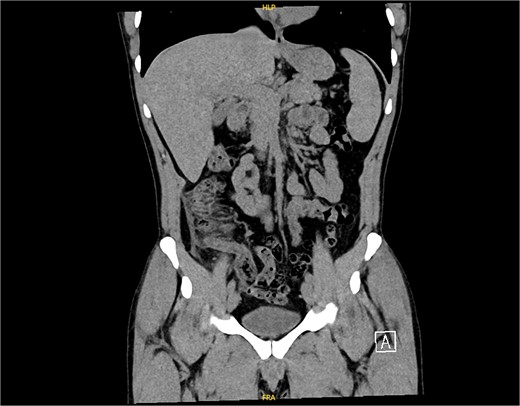

On examination, the patient was alert, oriented, and vitally stable. Abdominal examination revealed mild tenderness and rebound tenderness in the right iliac fossa. Laboratory investigations showed normal leukocyte counts and mildly elevated C-reactive proteins (38). An abdominal ultrasound suggested acute appendicitis or terminal ileitis (Fig. 1), prompting a CT scan despite the patient’s allergy to contrast.

An ultrasound picture showing tubular-like structure surrounded by edematous fluid.